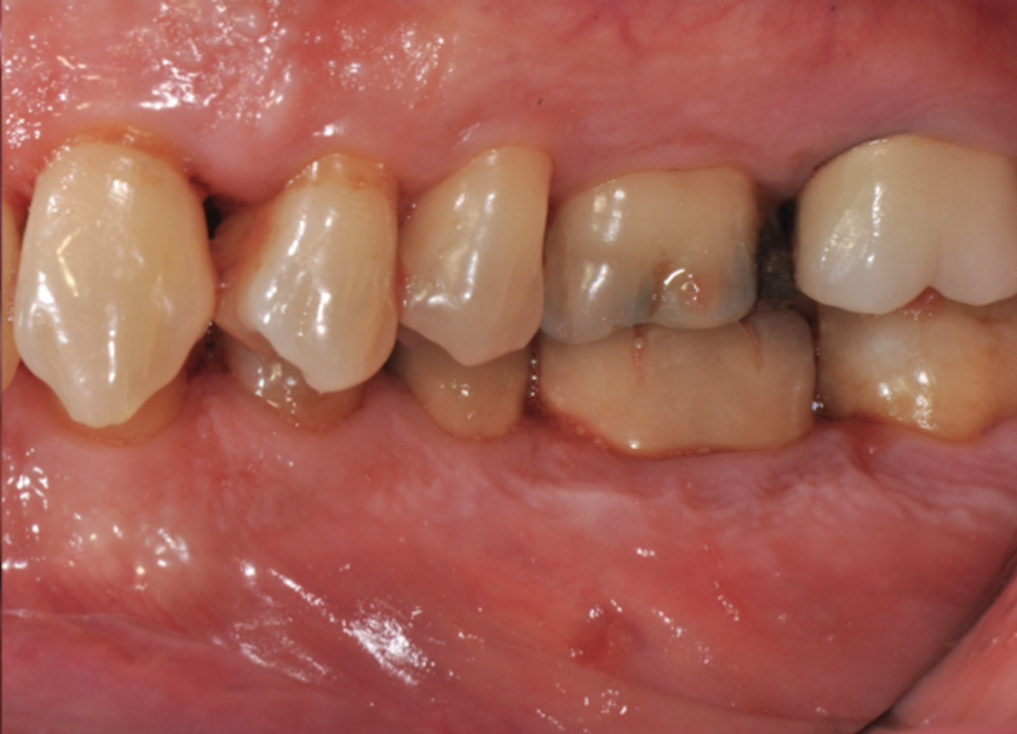

Fig 2. Pretreatment views: right lateral (Fig 2), frontal (Fig 3), and left lateral (Fig 4). Note: The maxillary right first molar (tooth No. 3) (Fig 2) would be identified as the most periodontally involved molar that was planned to be maintained.

Figure 2

Periodontal examination revealed generalized BOP and PDs up to 9 mm in the maxillary and mandibular molars with multiple furcations in each molar (Figure 2 through Figure 7). He presented with class I mobility in many posterior teeth and class II mobility in teeth Nos. 3 and 9 (maxillary right first molar and maxillary left central incisor, respectively). The periodontist decided to score tooth No. 3 for the PRS, as this was the most periodontally involved molar that was planned to be treated and maintained (Figure 2 and Figure 8). This tooth (maxillary right first molar = score 1) presented with probing depths of 7 mm (score 1); three total furcation invasions (score 3) (mesial [degree II furcation], buccal [degree I furcation], and distal [degree II furcation]); and a class II mobility (score 2). The total PRS for tooth No. 3 was 8, representing a "guarded" prognosis. Based on this score, the likelihood of not losing any teeth to periodontal disease for 15 years was 81%, and for 30 years the likelihood was just 56% (Figure 9).7